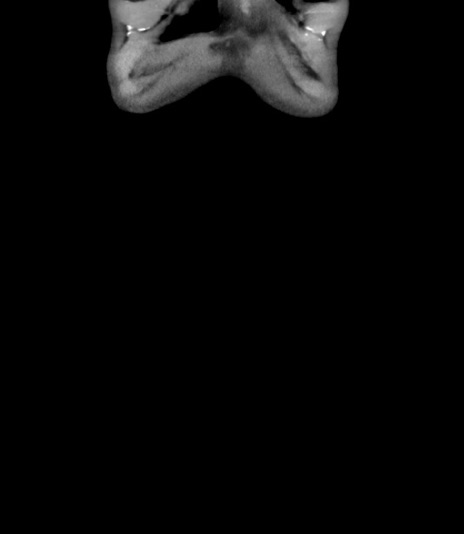

横断像